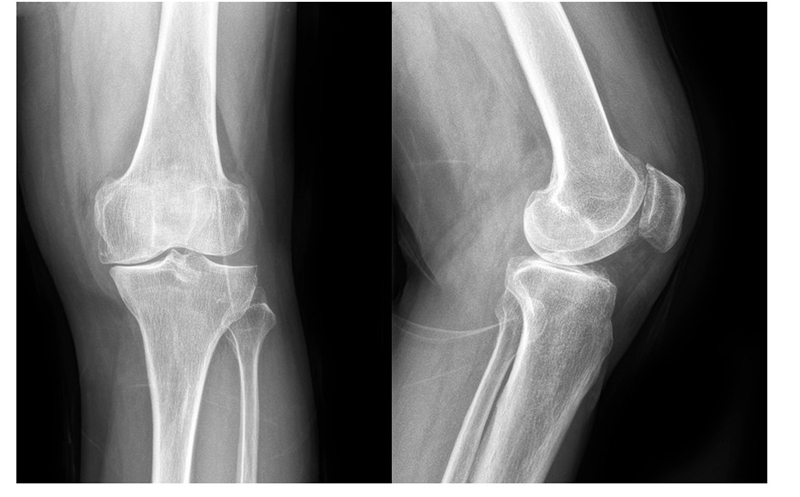

(1)70岁女性患者,以左膝关节疼痛5年、加重1年为主诉入院,入院查体左下肢内翻畸形11°,膝关节内侧间隙压痛阳性,外侧无压痛,髌骨研磨试验阴性,抽屉试验阴性,ROM 5°~120°,诊断左膝关节前内侧骨关节炎,行左膝关节内侧固定平台单髁置换术。术后给予预防感染、消肿止痛及抗凝治疗,术后24h康复师指导助行器辅助下床活动,术后1个月膝关节 HSS评分由63分升至85分,KSS评分由49分升至80分,内侧疼痛消失,患者恢复满意。手术前后影像学资料见图1~2。

图1术前 X线片示内侧间隙呈骨对骨改变